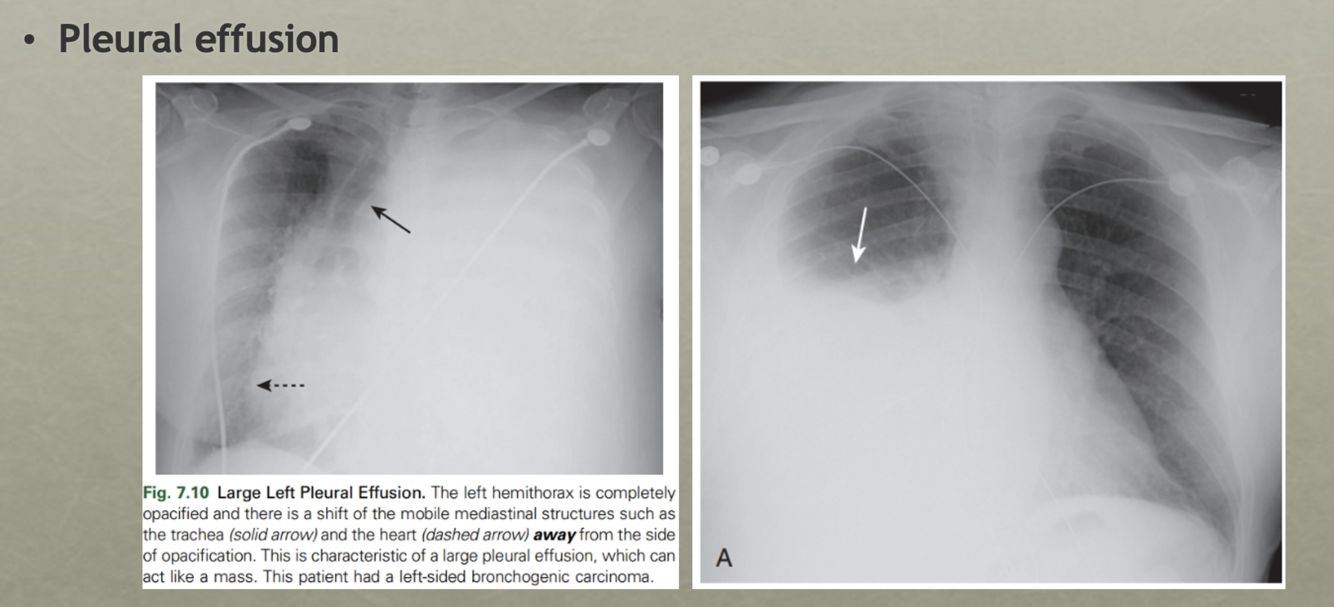

Pleural effusion

* Pleural effusions collect in the potential space between the visceral and parietal pleura and are either transudates or exudates, depending primarily on their protein content and LDH concentration

Very large pleural effusions may behave like a mass and produce a shift of the mobile mediastinal structures (i.e., the heart) away from the side of the effusion

Q

This is a pleural effusion

Notice the L side has the pleural effusion and the trachea is deviated the the R (because things are deviated away from the side w/ the pleural effusion)